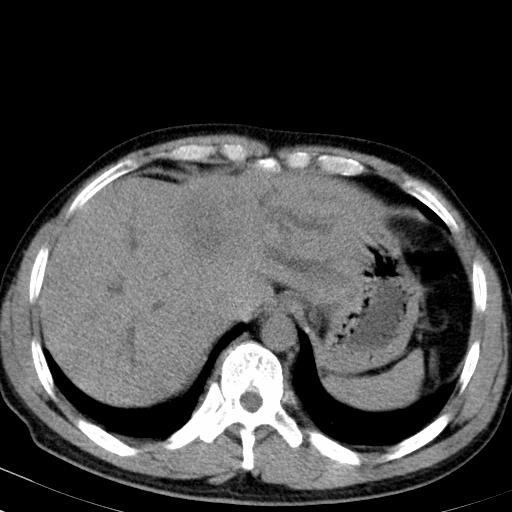

患者上腹部疼痛一月余,伴巩膜黄染;

实事求是的说,强化效果很一般,重点部位应重点观察,但有一点可以明确:肝门部胆管细胞癌。

考虑肝左叶胆管细胞癌侵犯肝门区并肝内胆管及肝总管扩张。

肝左叶肿块清度增强,所在的叶胆管扩张。考虑胆管细胞癌。

考虑肝左叶胆管细胞癌侵犯肝门区并肝内胆管及肝总管扩张、肝门淋巴结肿大。